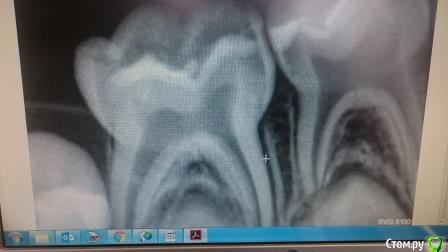

kuznetsova2908 Опубликовано 14 мая, 2017 Автор Поделиться Опубликовано 14 мая, 2017 Мы тут экспертизой не занимаемся. Что беспокоит ребенка?P.s. снимок в pdf это жесть Снимок только такой есть(( ребенка пока ничего не беспокоит, пломба поставлена 6 дней назад, о некачественном лечении мне сказала стоматолог в другой поликлинике, она лечила другой зуб, но предложила сделать снимок и этого и сообщила, что пломбой закрыта не вся пролеченная полость.Теперь боюсь, что со временем это может вызвать воспаление, если это действительно так, да и жаль потраченных на это средств и нервов ребенка (если перелечивать) Ссылка на комментарий

kuznetsova2908 Опубликовано 15 мая, 2017 Автор Поделиться Опубликовано 15 мая, 2017 (изменено) Мы тут экспертизой не занимаемся. Что беспокоит ребенка?P.s. снимок в pdf это жесть Дело в том, что мы лечили его в одной клинике, потом пошли в другую, где нам и предложили сделать снимок и прокомментировали тем, что полость не полностью запломбирована и может быстро развиться воспаление.Поэтому и прошу взгляда незаинтересованного в получении прибыли при перепломбировке.Прикрепляю снимок в пдф, но плохого качества( Изменено 15 мая, 2017 пользователем kuznetsova2908 Ссылка на комментарий

red_butler Опубликовано 15 мая, 2017 Поделиться Опубликовано 15 мая, 2017 только по одному снимку ничего не скажешь, не все материалы рентгеноконтрастные и видны на снимках Ссылка на комментарий

kuznetsova2908 Опубликовано 15 мая, 2017 Автор Поделиться Опубликовано 15 мая, 2017 только по одному снимку ничего не скажешь, не все материалы рентгеноконтрастные и видны на снимках Спасибо за ответ! подскажите, что необходимо предпринять в таком случае? Зуб 84(на снимке справа) кариес между зубками, темное пятно под пломбировочным материалом не говорит 100% об оставленной полости? Ссылка на комментарий

red_butler Опубликовано 15 мая, 2017 Поделиться Опубликовано 15 мая, 2017 Спасибо за ответ! подскажите, что необходимо предпринять в таком случае? Зуб 84(на снимке справа) кариес между зубками, темное пятно под пломбировочным материалом не говорит 100% об оставленной полости?сходите еще на одну консультацию Ссылка на комментарий